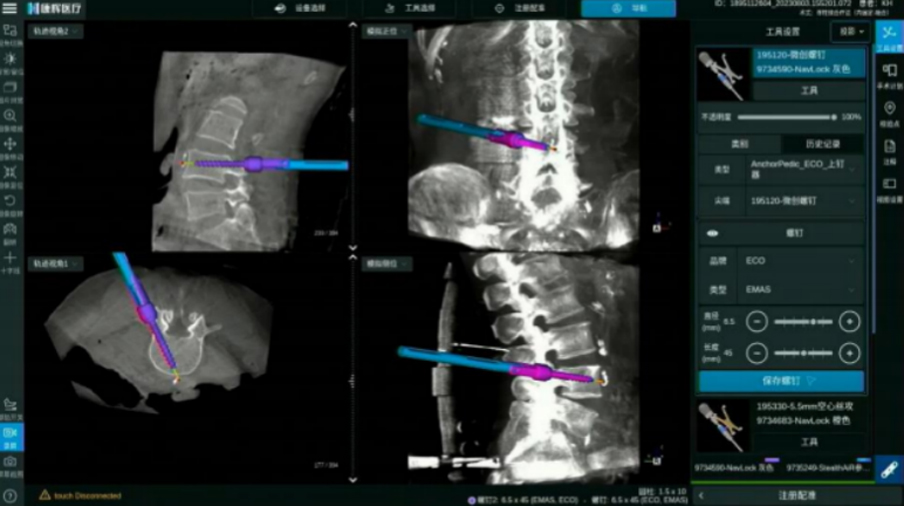

頸椎后路內固定

全程可視化帶來頸椎手術精準性的提升

全流程可視

精準,看得見!

ECO/Anchor與導航化學連接 螺紋級可視

電動手柄配合導航實現可視化動力置釘

· 無導絲置釘流程, 手術更加精準安全

· 開路、絲攻、置釘,手術全程步步實時可視

· 實時呈現手術工具、 內植入物清晰邊界

· 可拓展至椎間處理步驟 三維實時可視